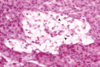

Histology of a pancreas from a cat with Diabetes mellitus due to:

Insulin Antagonism